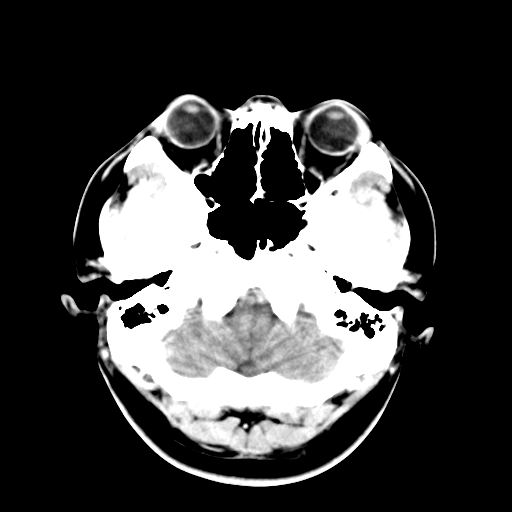

标题: CT16447B:(续)增强扫描图像。

患者今日做ct增强检查,现补传增强扫描图像。

松果体钙癍增大,无其他改变,定不了性

一般认为大于1cm为异常。